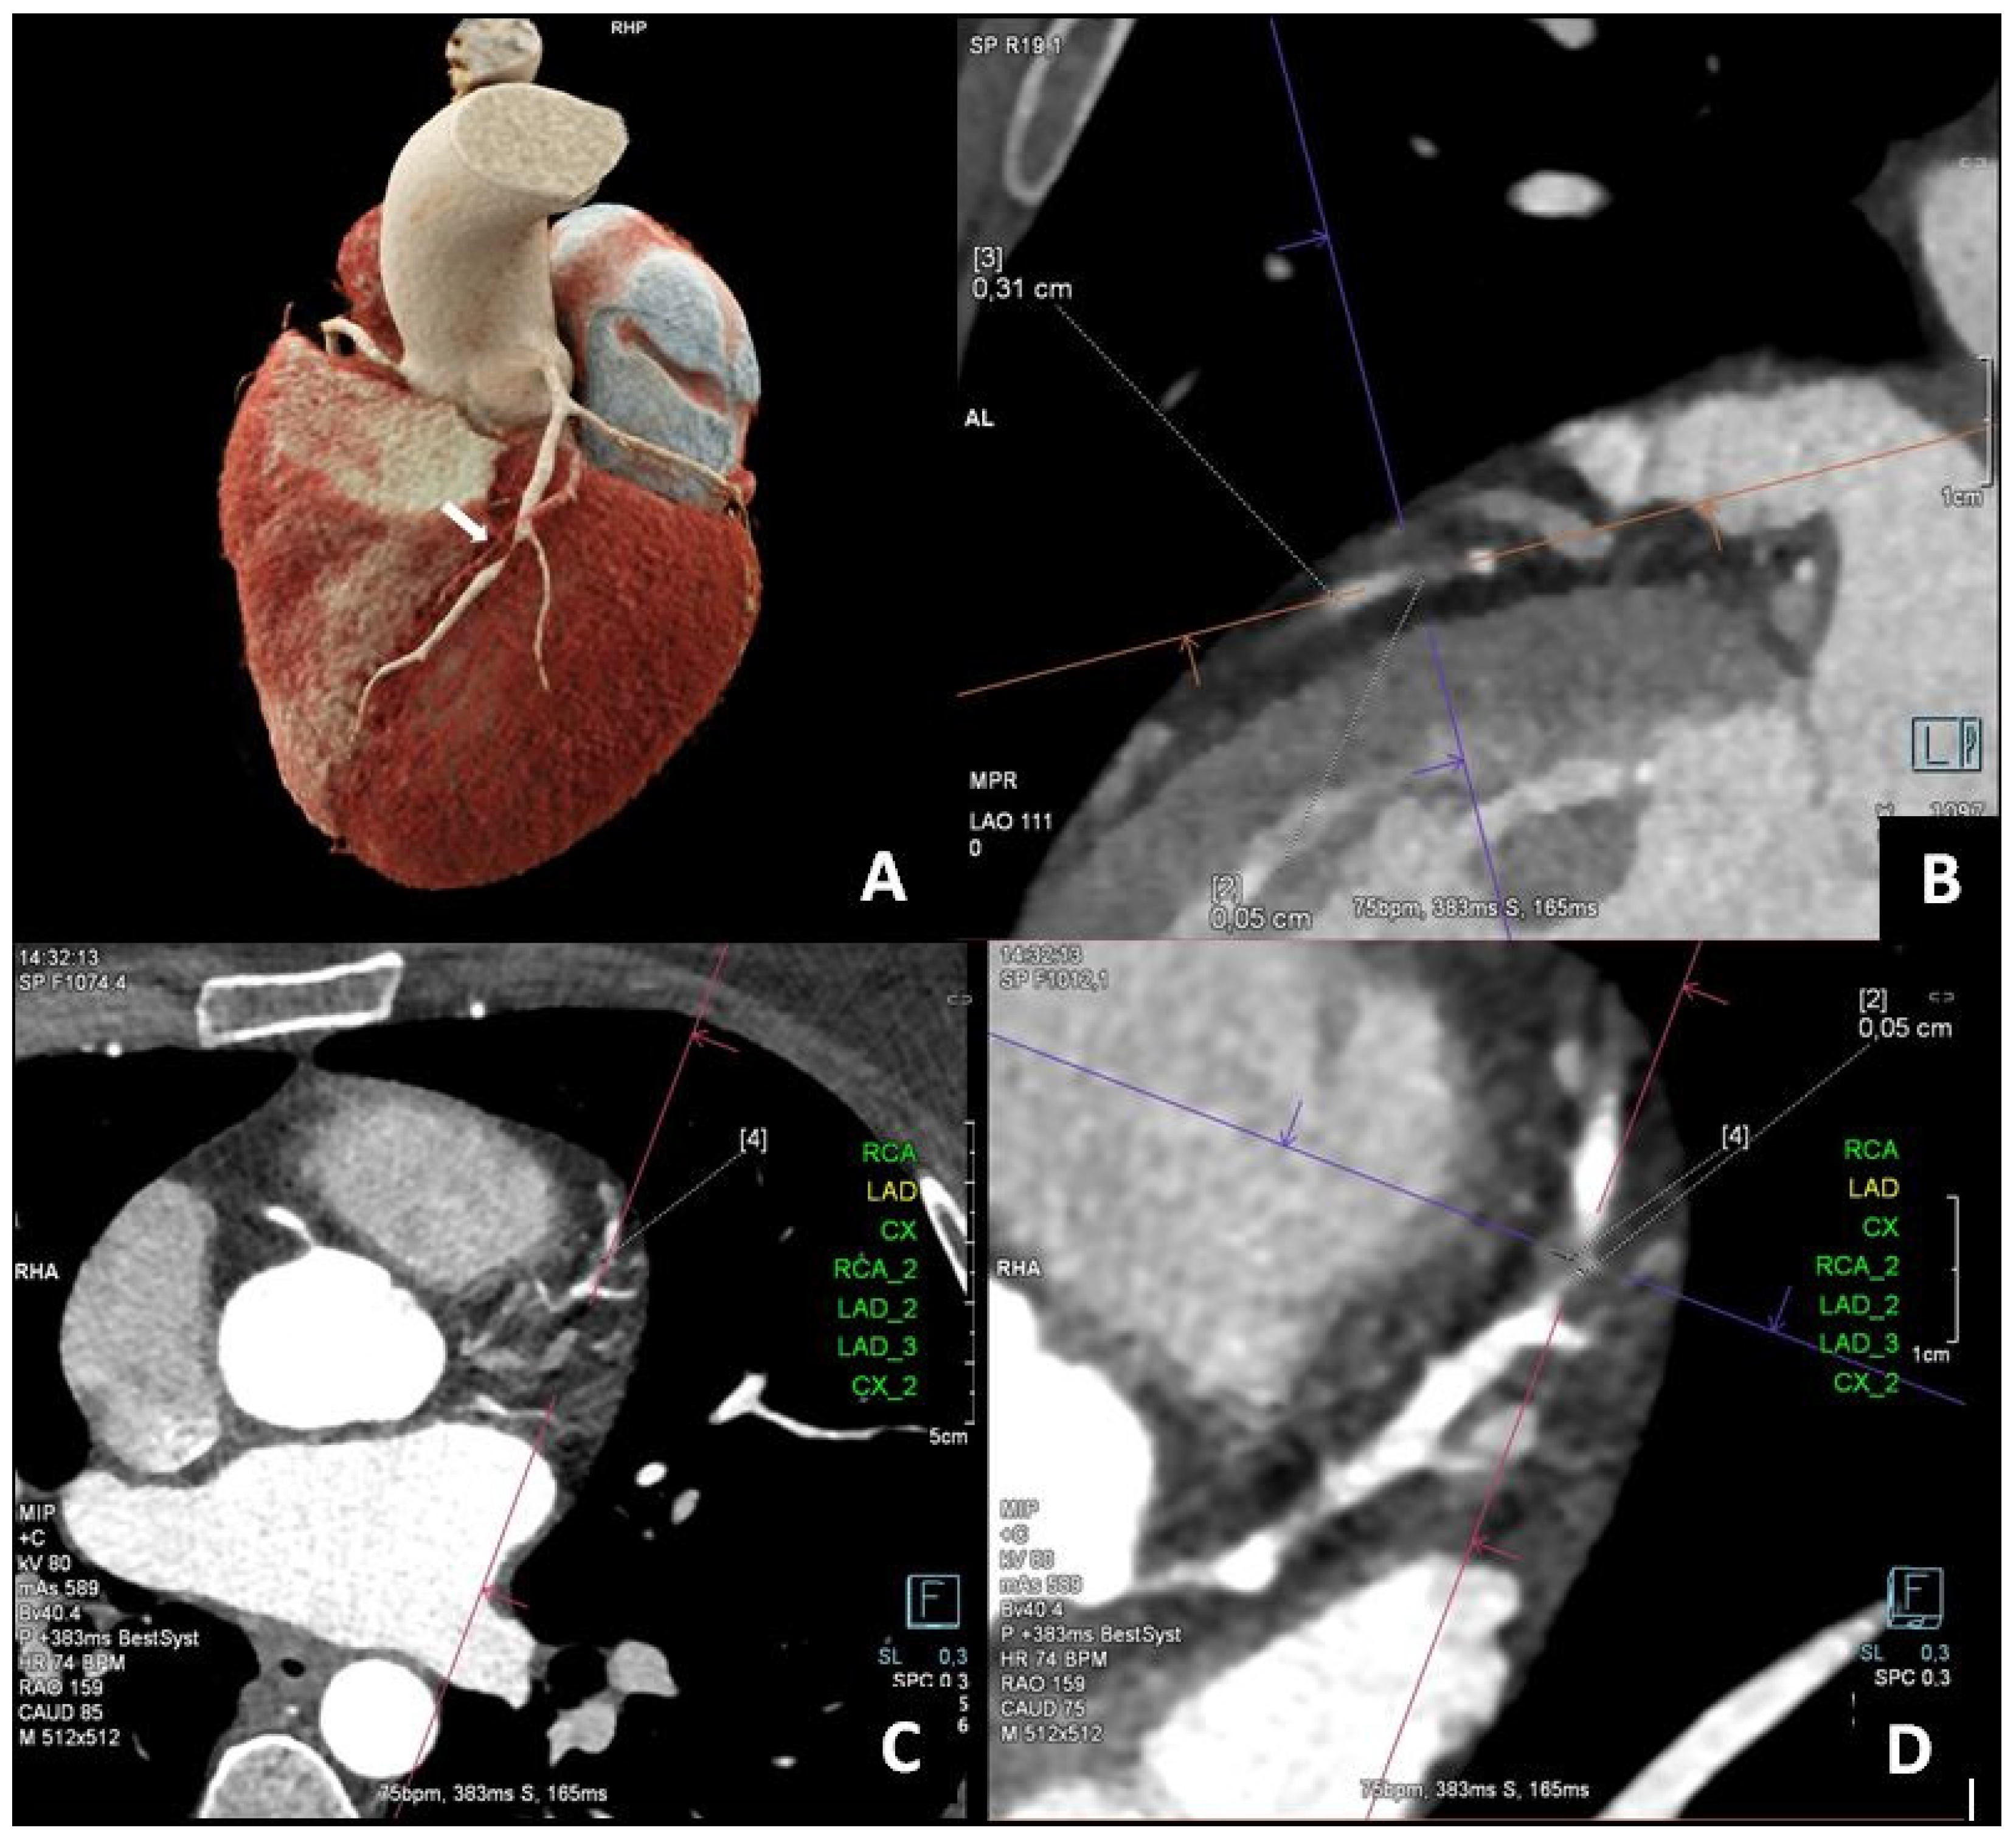

Computed Tomography, Coronary Angiography, and Intravascular Ultrasound in the Diagnosis of Left Anterior Descending Stenosis in a 38-Year-Old Woman with a Calcium Score of Zero

- Wojciechowski, A.; Zarotyńska, M.; Chyrchel, B.; Terlecki, M.; Wojciechowska, W.; Rajzer, M. Zero calcium score: A potential pitfall in the diagnosis of coronary artery disease. Pol. Arch. Intern. Med. 2025, 135, 16936. [Google Scholar] [CrossRef] [PubMed]